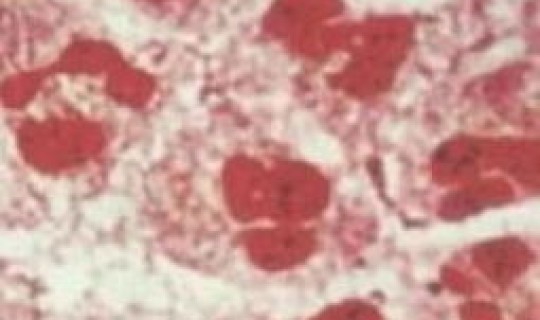

分泌物涂片检查:医生会取患者尿道口 、宫颈口或其他可能感染部位的分泌物 ,放置在显微镜下进行观察。在淋病患者中,白细胞内常会出现革兰染色阴性双球菌,这是淋病奈瑟菌的典型特征 。此检查 *** 操作简便、快速,是初步筛查淋病的常用手段。但需注意 ,其特异性相对较低,可能受到其他因素干扰,出现假阳性或假阴性结果。

医生会从患者可能感染的部位(如尿道、 *** 、 *** 或宫颈)采集分泌物样本,通过革兰氏染色后在显微镜下直接观察是否存在淋病奈瑟菌 。该 *** 操作快速、成本低,但敏感性有限,可能因样本中细菌数量不足或存在其他微生物干扰而出现假阴性结果 ,通常作为初步筛查手段。